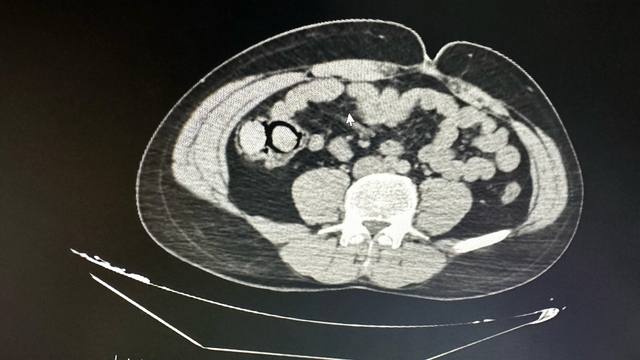

İl Emniyet Müdürlüğü Narkotik Suçlarla Mücadele Şube Müdürlüğü ekipleri tarafından gerçekleştirilen operasyonda, uyuşturucu ticareti yapmak üzere kente otobüsle geldiği bilgisine ulaşılan 2 şüpheli gözaltına alındı. Şüphelilerin hastanede yapılan muayenelerinde, midelerinde toplamda 10 parça halinde 113 gram metamfetamin maddesi ele geçirildi. Şüphelilerin midelerindeki uyuşturucu paketleri, hastanede yapılan işlemle çıkarıldı. Emniyetteki işlemlerinin ardından adliyeye sevk edilen şüpheliler, sevk edildikleri adliyede çıkarıldıkları mahkemece tutuklanarak cezaevine gönderildi.